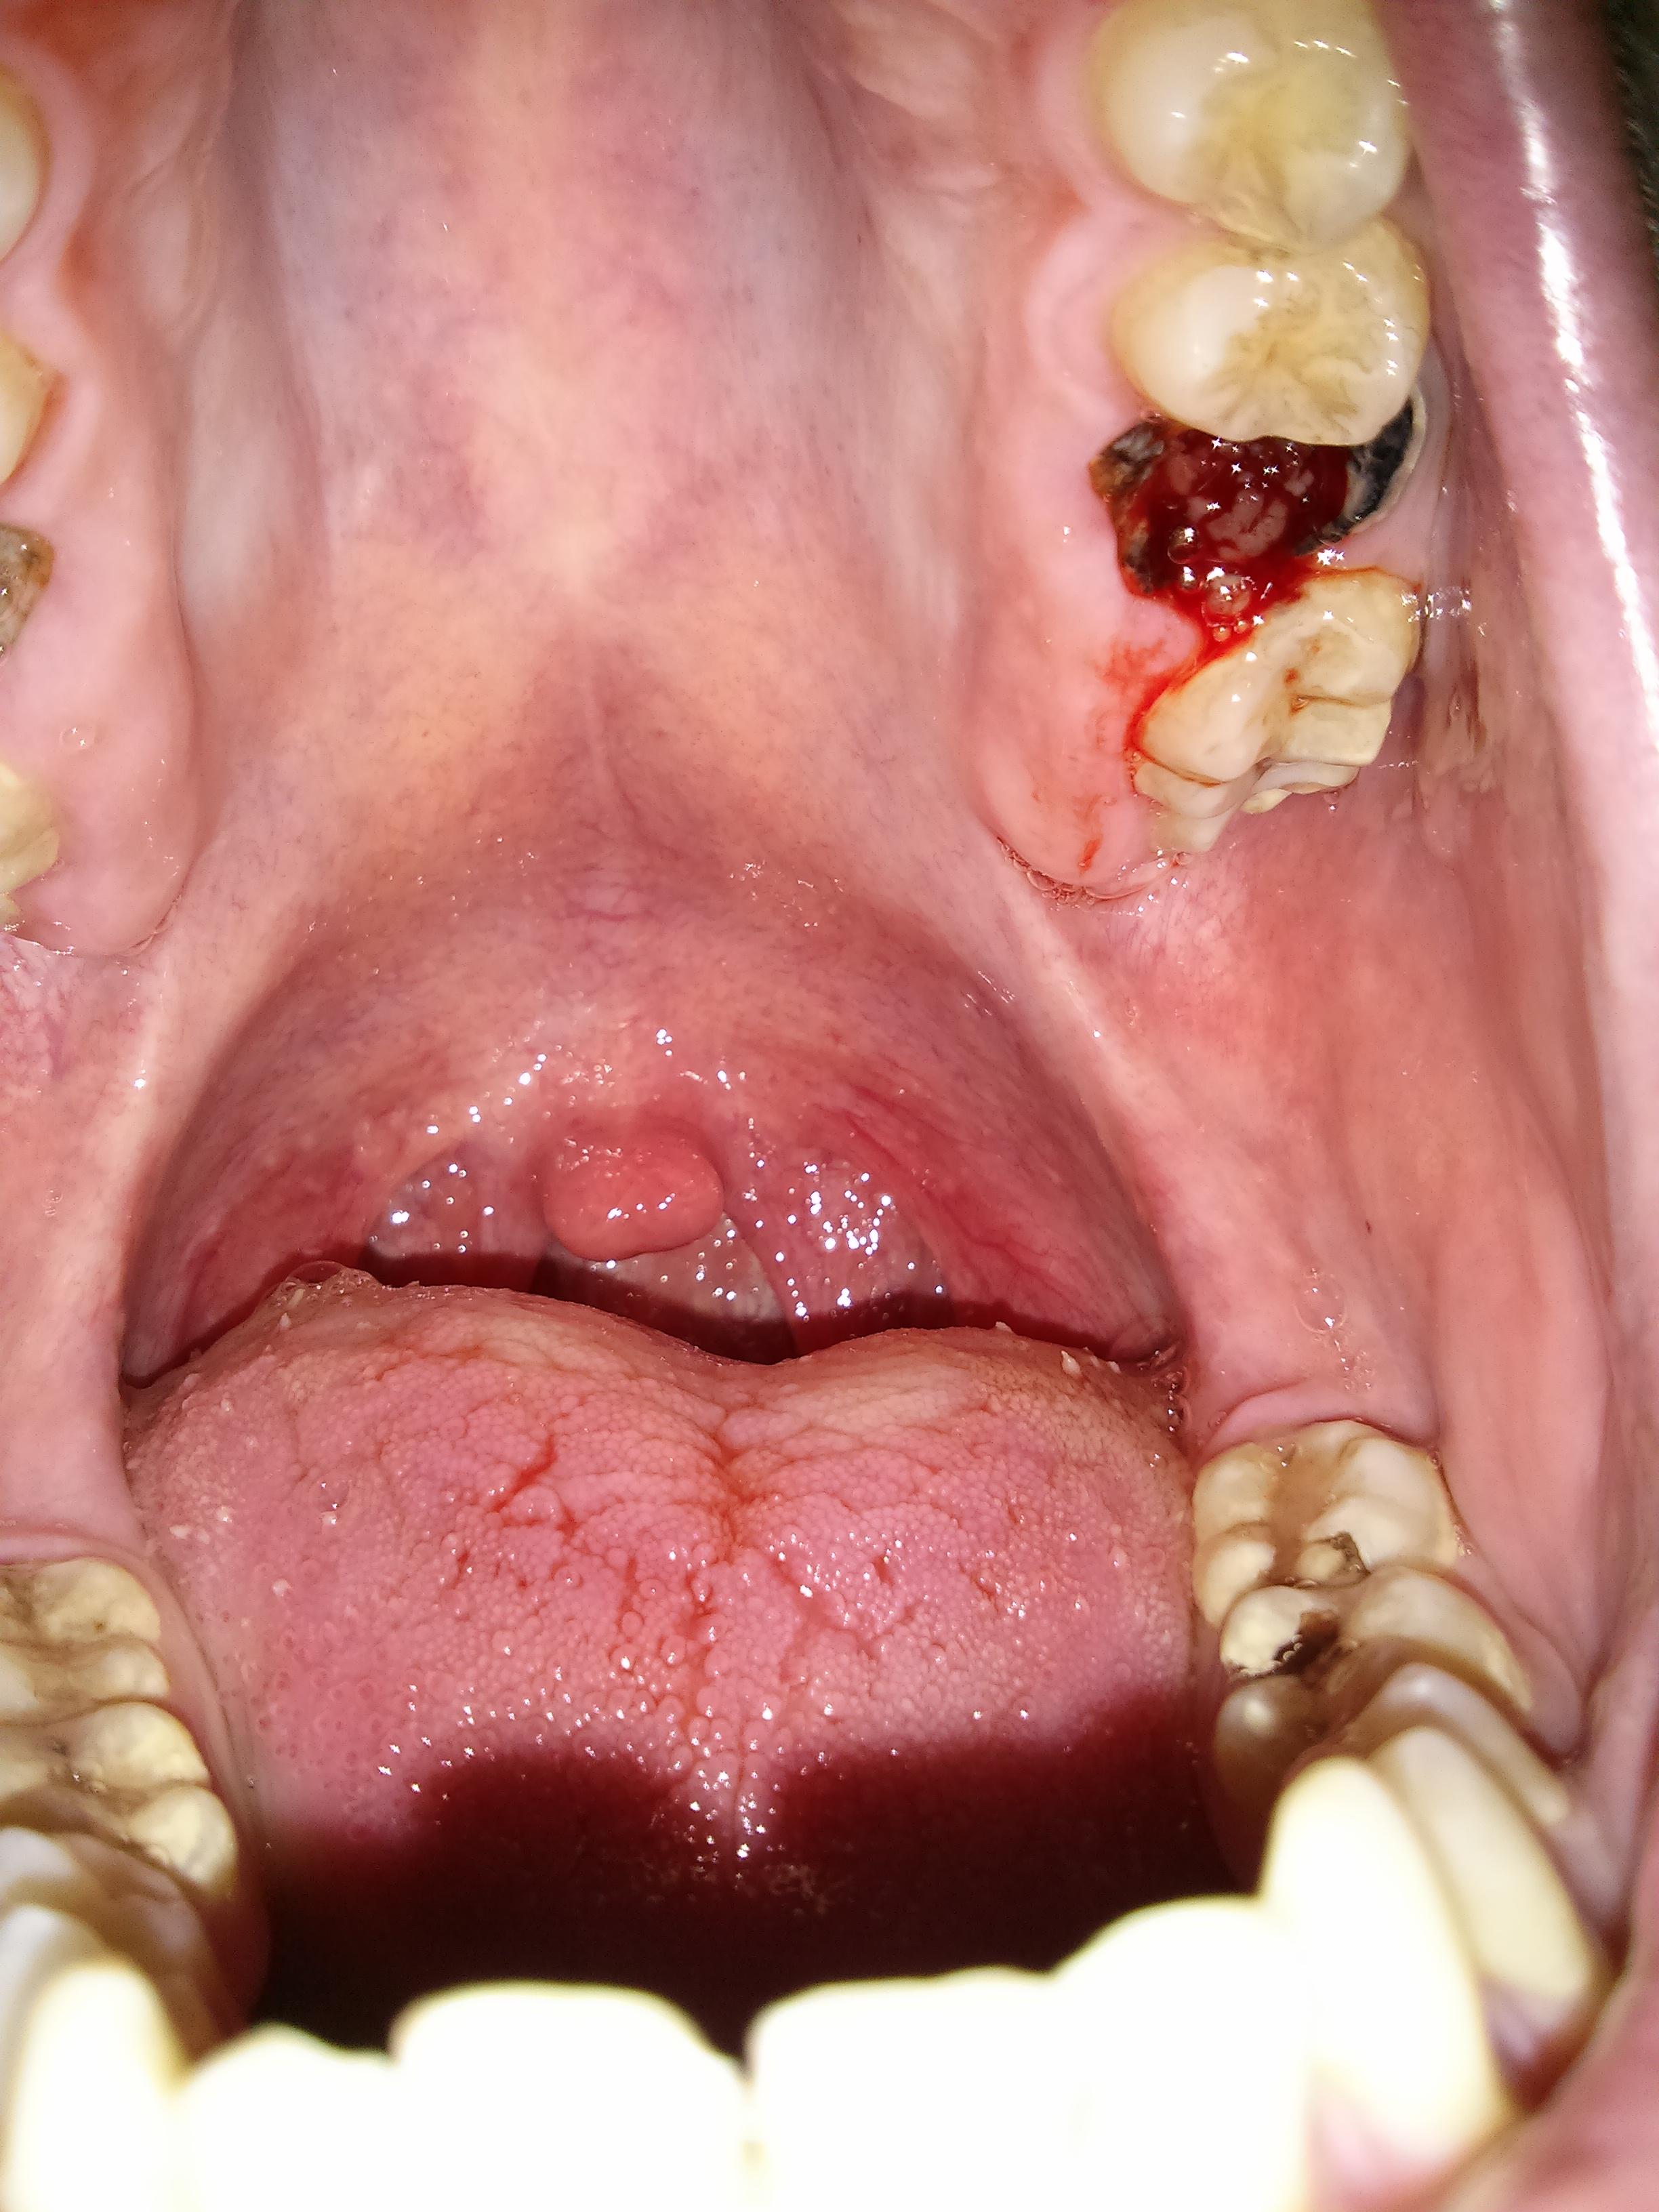

Аноним Срд 19 Мар 2014 00:30:53  #1 №64592832

1395174653819.jpg

Постим ИТТ свои зубки. Имею две вот такие неприятности. Что делать, куда бежать?

Бампец зияющей дырой.

У тебя язык в трещинах.

Я чета не понял. Если зуб удалили, то черноты быть не должно. Если у тебя просто настолько разрушился зуб, то не должно быть крови.

Нет, мне было похуй и за какой-то годик-второй он полностью сгнил.

А кровь откуда?

Прогнило почти до конца, лол.

>>64593442

Когда-то мне рвали зуб и умудрились каким-то макаром повредить при этом челюсть. БЫЛО ПИЗДЕЦ КАК БОЛЬНО! Из-за этого теперь люто боюсь, ну и мой врожденный похуизм, да. Да и к тому же дыры эти не болят вовсе.

>>64593956

Закажи виниры

Трипуй под кетамином

Аноним Срд 19 Мар 2014 00:56:24  #46 №64594328

50-летняя толстая бабища старой дохрущевской совковой закалки.

Аноним Срд 19 Мар 2014 01:07:02  #75 №64594903